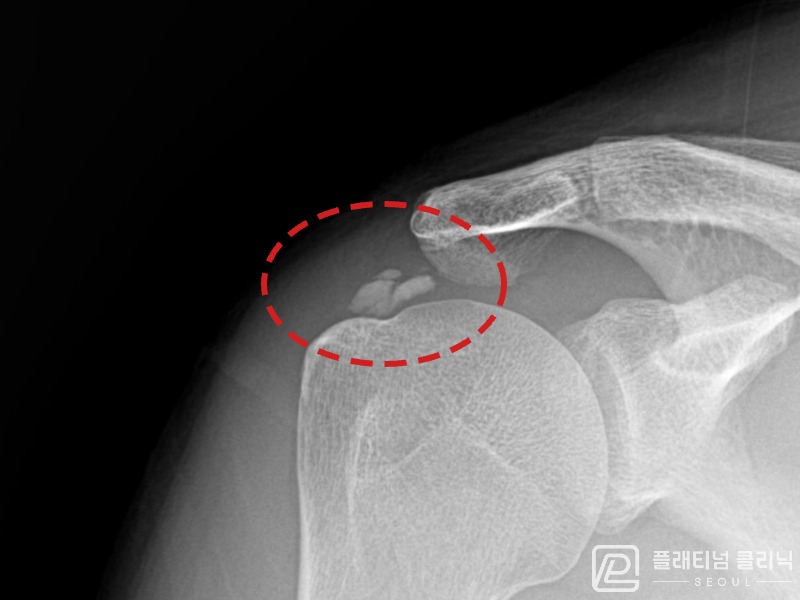

[촬영시기:21.10.21~21.10.30]

[석회분쇄흡입술] 우측 어깨 통증과 운동 제한으로 일상생활이 불편해진 30대 여성 환자로, X-ray에서 우측 극상근건 내 석회 침착이 확인되어 석회분쇄흡입술을 시행하였습니다.